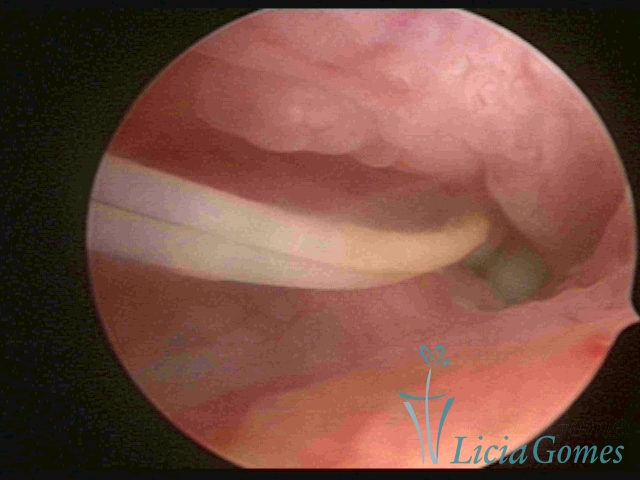

Canal cervical com fio do DIU